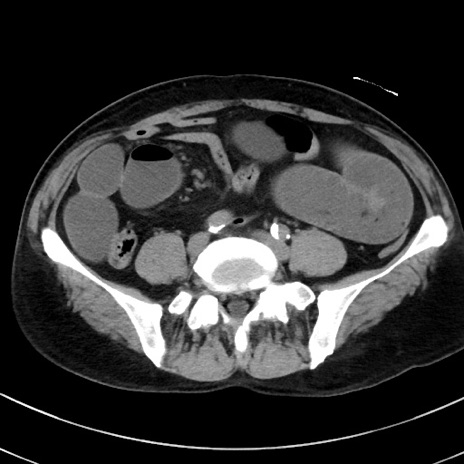

症例38(横断像)

【症例】70歳代 男性

【主訴】腹痛・嘔吐

【現病歴】昨晩より、嘔吐・腹痛あり。今朝になっても嘔吐あり。来院。

【既往歴】心臓バイパス手術、開腹胆摘、腸閉塞

【身体所見】BP 107/71mmHg、HR 116/min、腹部:平坦、軟、下腹部に軽度圧痛あり。反跳痛なし。

【データ】WBC 15100、CRP 0.32